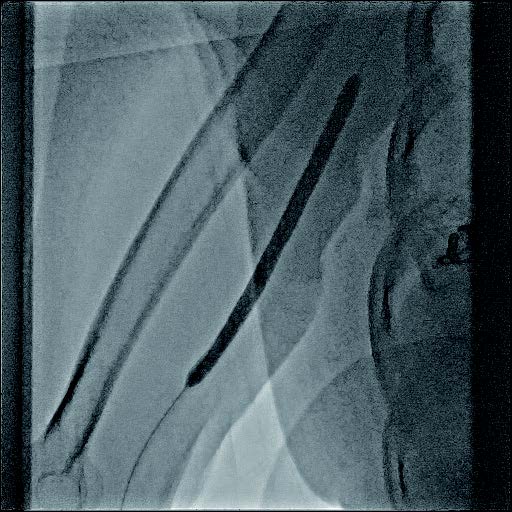

- PTA バルーンカテーテル:径6 mm×長100 mm

- ステントグラフト:バイアバーン® ステントグラフト 径7 mm×長100 mm

バイアバーン® ステントグラフト留置の手技については、当施設では概ね毎回同じ手技を実施している。ステントグラフトの長さについては病変に依存するが、径については6 mmの人工血管に対して、7 mmのバイアバーン® ステントグラフトを留置している。

静脈とはいえ、透析患者においては硬化性変化が強い病変が多く、indentation を残さずに pre dilatation をかけておくことが重要と考えられる。そこで、径7 mmのバイアバーン® ステントグラフト留置前に、径6 mmの高耐圧バルーンにてしっかり拡張し、indentationを残さないことを確認した。バイアバーン® ステントグラフト留置後もバルーンでステント内、特に人工血管とのオーバーラップ部位にしっかり圧をかけて後拡張を行っている。